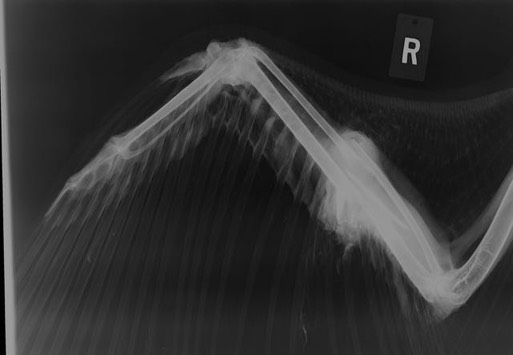

Bald Eagle 17-659

A juvenile Bald Eagle was found in an orchard near Eltopia, WA. The finders thought it had a broken wing and a broken leg. An exam confirmed the fractures. the mystery is they appear to have occurred at different times. The wing fractures look old. There is significant callus formation and the fractures appear to have been caused by gunshot. The leg fracture appears to be very recent and shows no sign of being caused by gunshot. Unfortunately the damage was too extensive to be successfully repaired, and the bird was euthanized.